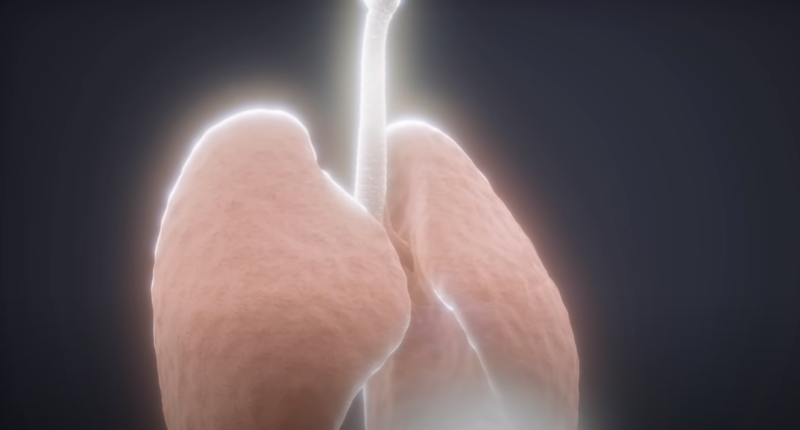

这里为了方便理解,需要看看我们正常的肺部:

肺内部有大量的树枝状气管,逐级变细,直到每个树枝的末端会有一个名叫肺泡的囊状结构。这种富有弹性并且表面布满毛细血管的结构是我们呼吸氧气并排除二氧化碳的基础。

但是,由于战斗的持续,血管通透性增强,血液渗入肺泡,同时在肺泡内会分泌大量黏液。

如果在这个时候,对患者肺部进行CT扫描,我们会看到像下面这样大面积白色区域,医学上称之为“白肺”。这样肺部失去了原有的交换气体功能,最终使正常呼吸变得异常困难。